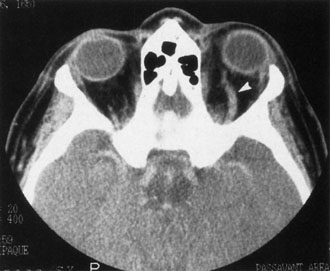

Contrast-enhanced CT of the orbits with direct and coronal cuts is the radiologic study of choice for these patients.45 A well-demarcated, encapsulated oval or rounded mass is revealed, which is typically intraconal in the lateral part of the middle third of the orbit (Fig. 5) but occasionally may extend to the extraconal space.42 Septa within the tumor may be apparent on high-resolution CT. The posterior pole of the globe frequently is indented by the rounded anterior margin of the tumor.42 The optic nerve typically is displaced rather than surrounded by the tumor. Subtle outward bowing of the lateral orbital wall or increase in orbital size may be present, consistent with a long-standing, slowly growing mass lesion.10,42 Enhancement with intravenous contrast occurs and may be homogeneous or inhomogeneous.10,45 Rarely, cavernous hemangiomas may occur as an intraosseous tumor within the orbital or facial bones.42,53–55 Although usually an isolated intraorbital lesion, multiple lesions in one orbit occurred in 8 of 164 (5%) patients of three combined large studies,10,42,45 and bilateral multiple cavernous hemangiomas also have been described.56 In contrast to patients with venous flow malformations in which phleboliths are common, phleboliths are rare in cavernous hemangiomas. Three large studies comprising 164 patients with cavernous hemangioma all reported that no calcification was detected within the tumor.10,42,45If the diagnosis is still unclear or if better definition of details and localization of the lesion is required, then MRI should be performed. Magnetic resonance imaging demonstrates nonspecific characteristics of a lesion isointense to muscle and gray matter on T1-weighted images and hyperintense on T2-weighted images (Fig. 6).57 The lesions show initial central patchy enhancement, which fills up homogeneously within 20 to 60 minutes.58 If ultrasonography is performed, B-scan ultrasonography shows a well-circumscribed mass with a sharply defined anterior acoustic border.23 A-scan ultrasonography shows high reflectivity of the echo signals resulting from the multiple blood-filled vascular channels, regular internal structure with a higher anterior and posterior spike marking the capsule, and moderate sound attenuation (angle of decrease of the echo spike within the lesion).24 Arteriography is not indicated.

Fig. 5. Cavernous hemangioma. Contrast-enhanced axial computed tomography scan shows a well-demarcated, oval intraconal mass in the lateral part of the middle third of the orbit. Note the enhancement within the lesion, which in this instance is inhomogeneous, but can also be homogeneous.